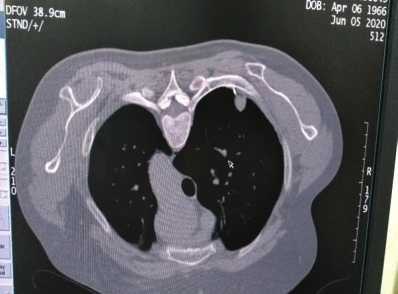

家住咸安青龙巷的金女士因宫颈癌,在武汉协和医院行规范治疗近一年后,于今年4月复查发现右肺上叶后段结节,性质待定。考虑到金大姐肺部结节较小,不到1cm,并且所处位置靠肩胛骨位置,想取活检明确病理难度极其高,武汉专家建议定期复查。由于病因尚不明确,金女士担心肿瘤复发,延误治疗,心情非常沉重且焦虑不安。

今年5月,在病友介绍下,金女士专程来到市中心医院,找到该院肿瘤科主任舒诚荣和章永医师,希望能得到两位医师的帮助。为了解除金大姐这块心病,两位医师在仔细阅片后,决定尝试使用自制带角度定位栅栏在CT引导下采取非共面经皮肺穿刺活检。

其中,该科所拥有的自制带角度定位栅栏在CT引导下经皮肺穿刺活检技术,是章永医师自行研发的一项新的应用技术,目前。该技术适用于肺部有病变的患者,如肿块,结节,软组织病变的患者,通过边做CT,并在自制带角度定位栅栏定位下,使得以往不易确定进针部位,能够精准确定肺部肿块进针穿刺位点,进行穿刺活检,取得肿块组织,送病理科行病理诊断,明确病变性质。